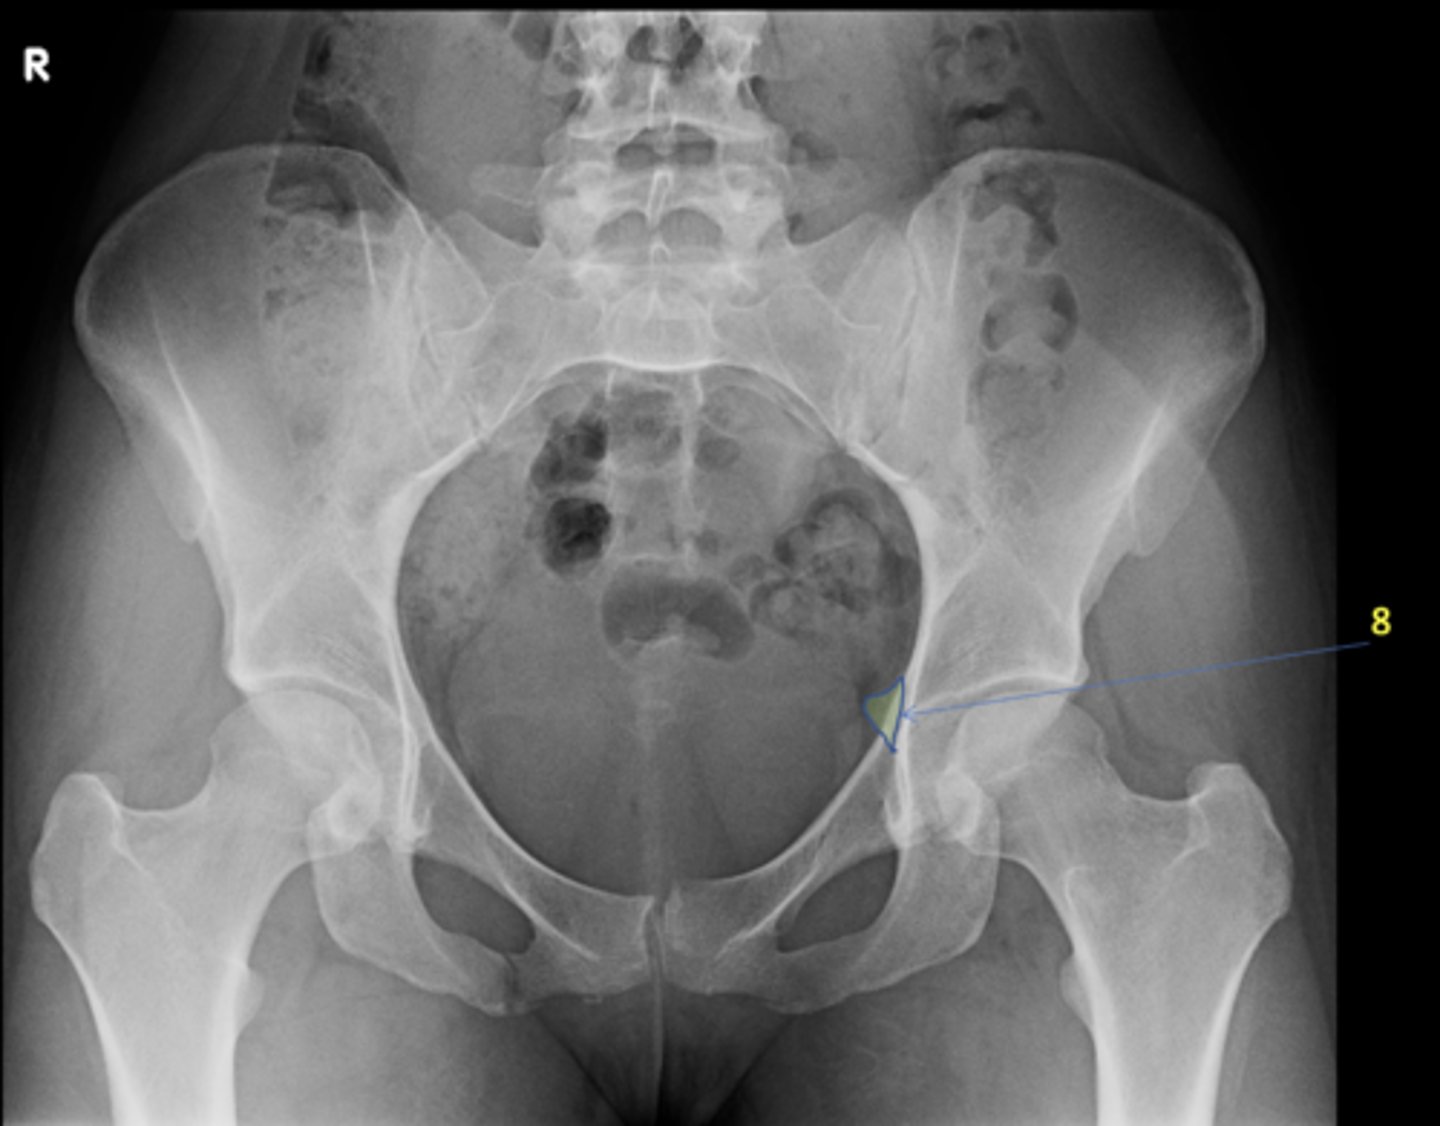

AP pelvis

View?

8

New cards

Left ischial spine

ID 8

<p>ID 8</p>

9

Right fovea capitis

ID 9

<p>ID 9</p>

ID 19

<p>ID 19</p>

Kohler's teardrop

ID 20

Right pubis

ID 21

Right anterior sacroiliac joint

ID 22 (joint)

Left superior pubic ramus

ID 24

Right acetabulum

ID 25

Right intertrochanteric crest

ID 26

Left ilium

ID 27

Right ischial tuberosity

ID 28

Bladder

ID 29

Ascending colon

ID 30